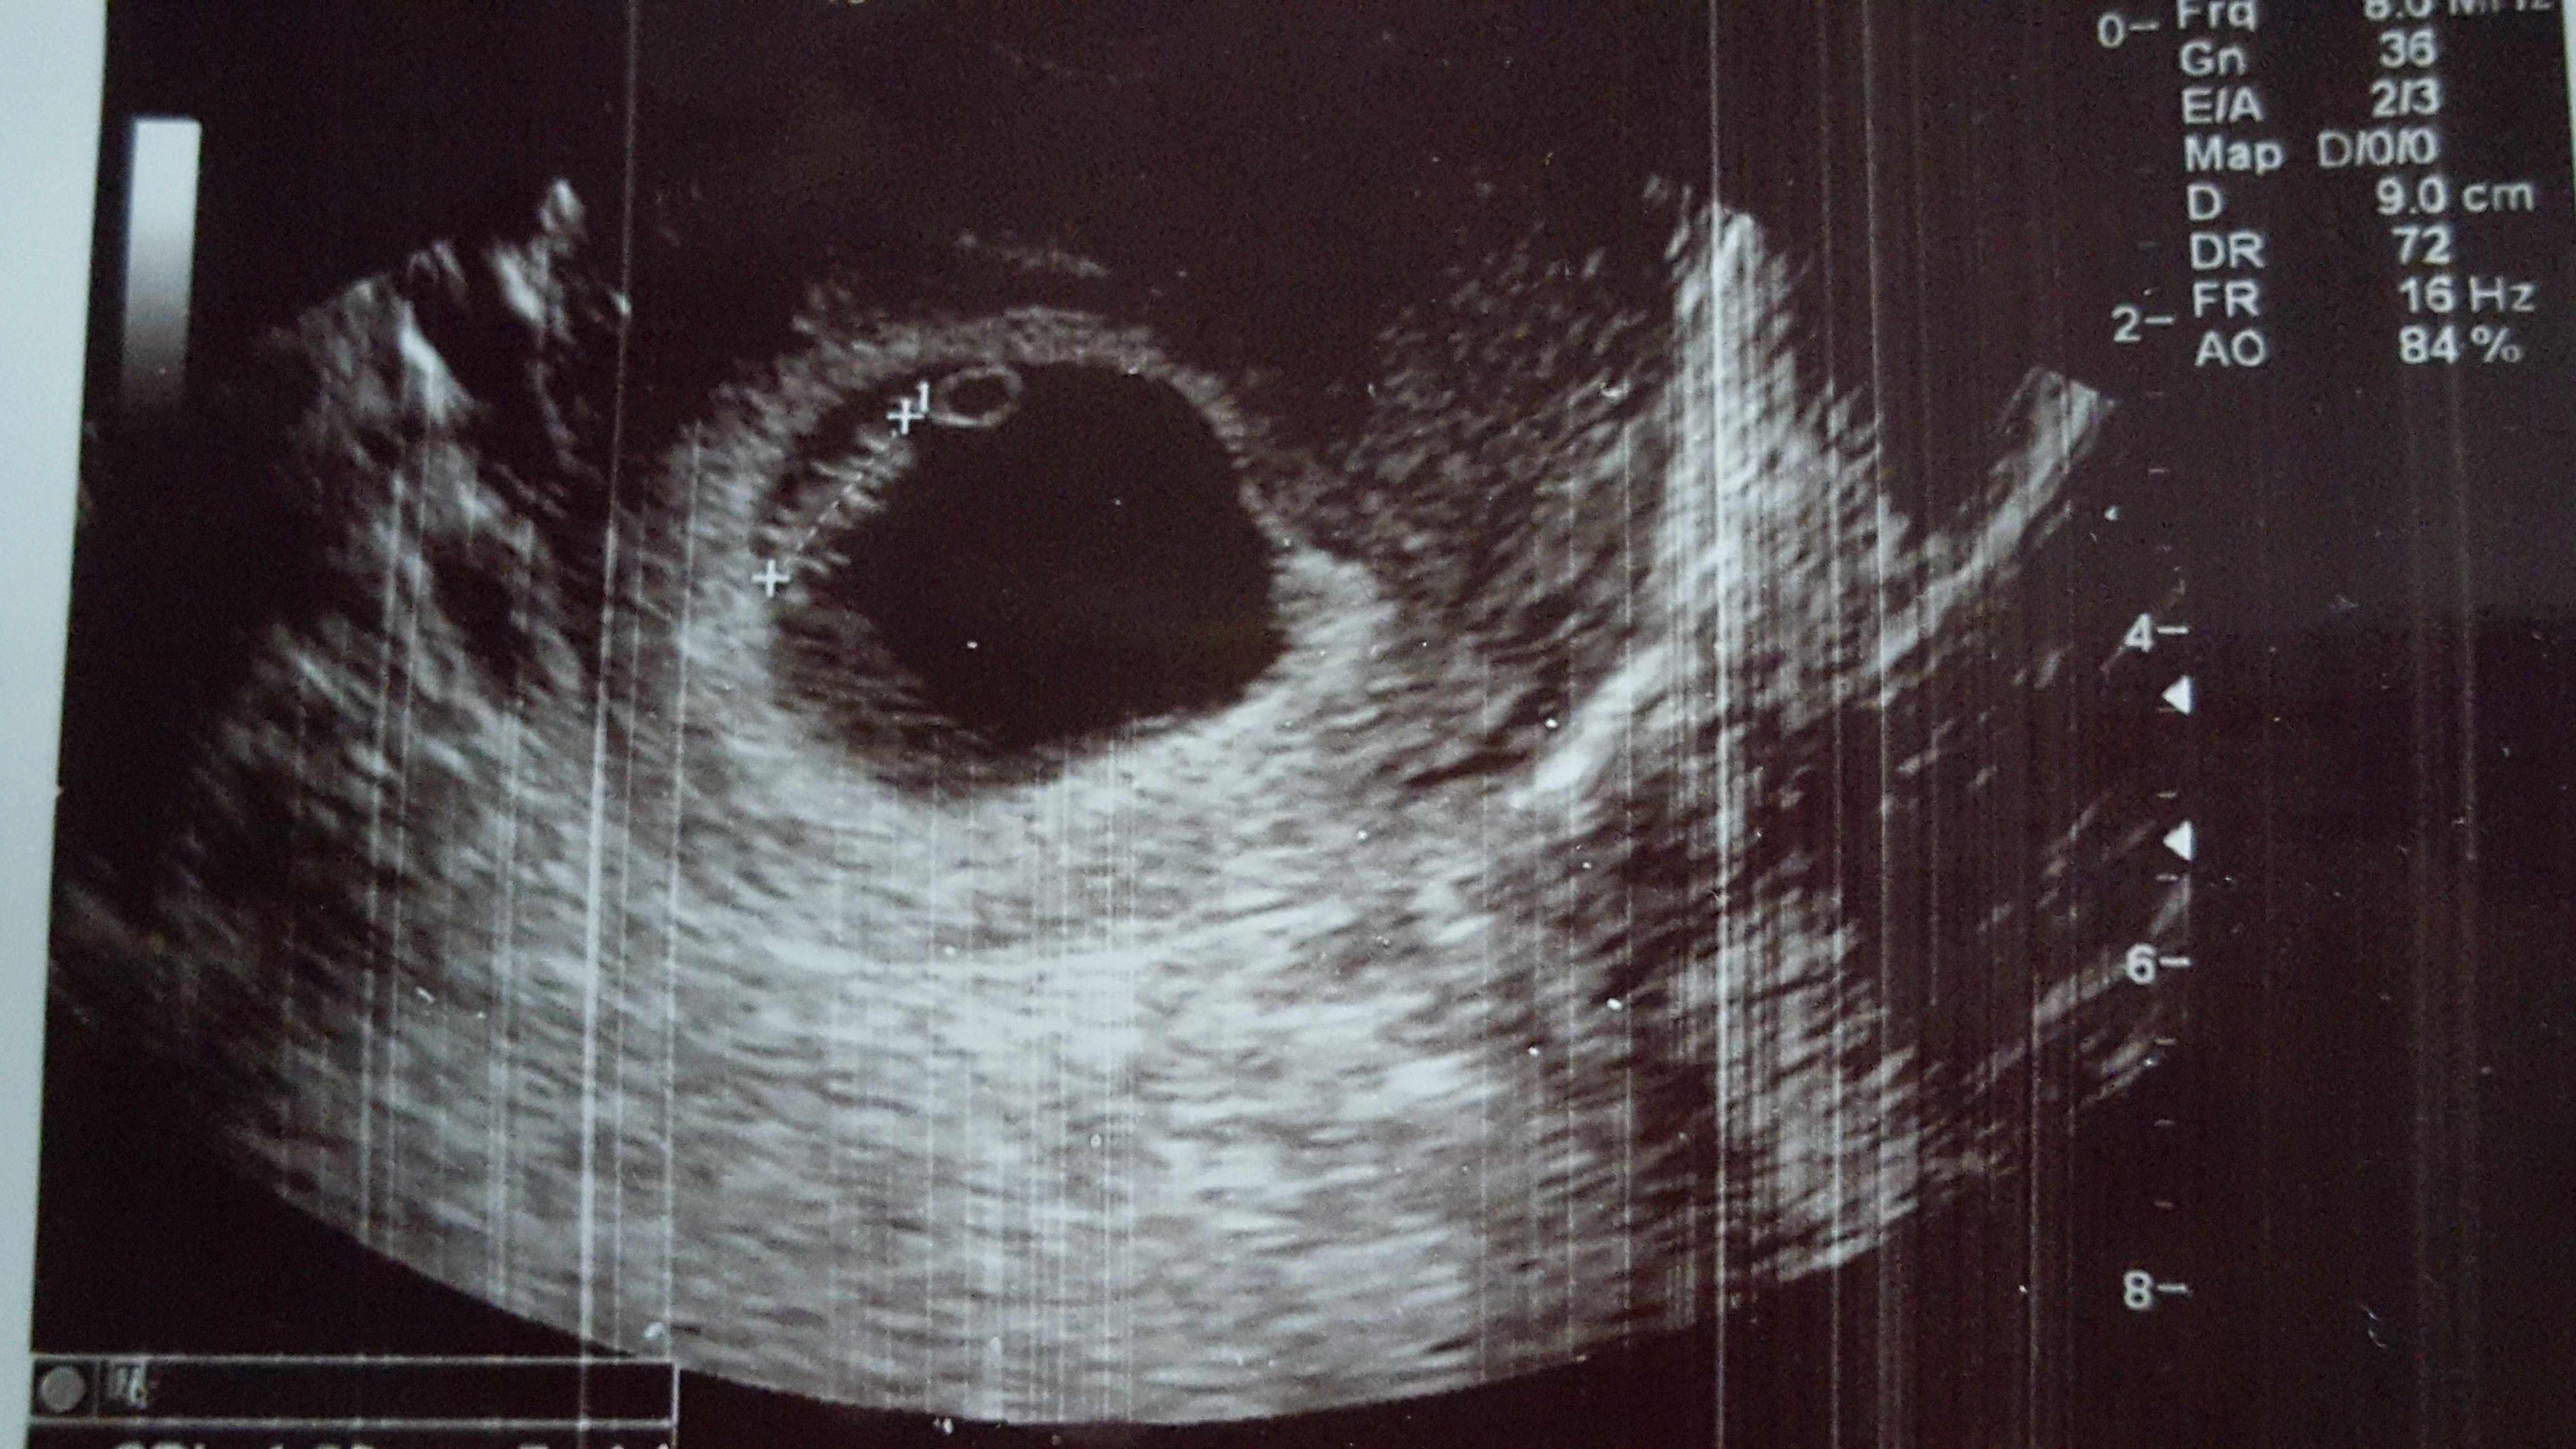

6w4d. Heartbeat at 140. Tech said ultrasound was messing up a bit, which could explain the "mirror twin". Guess we have to wait and see! (Anyone else have this issue?)

Tech said ultrasound was messing up a bit, which could explain the "mirror twin". Guess we have to wait and see! (Anyone else have this issue?)